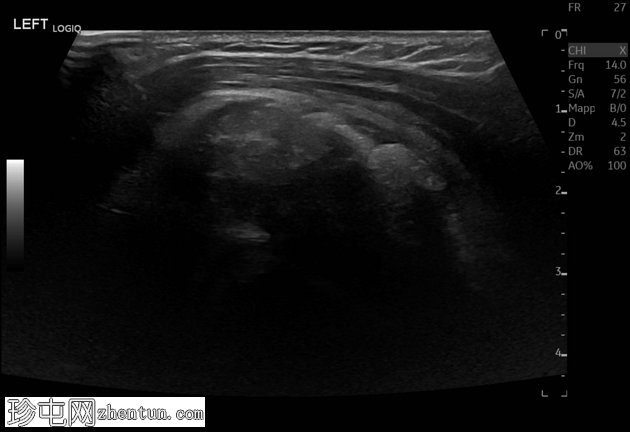

X线片

正位 -

可见肱骨头周围、三角肌腱和冈上肌腱之间有钙化沉积物,呈致密均匀的阴影。